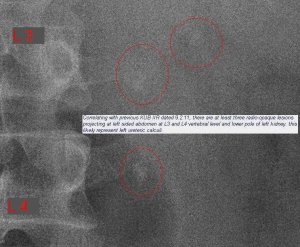

But the Urine FEME came back positive for RBCs, so my provisional diagnosis shifted towards urolithiasis. I downloaded the X-ray film and e-mailed it to a surgeon in Hospital Kuala Lumpur. He confirmed my suspicions by replying, “Congratulations, you got triplets!”.

The ultrasound report confirmed the diagnosis. I started treating myself by ingesting potassium citrate mixture 3 times a day to alkalinise my urine. I also had UFEME done regularly to monitor the presence of RBCs in the urine. A week later on 17th Feb, when the RBCs were no longer being detected in the urine, I had another KUB X-ray done.

The KUB on the 17th indicated that the bottom stone was still at the same site but the other two stones has come together and now were on top of each other. But there was no RBCs coming through, so either the bottom stone was blocking everything or the bottom stone had stabilised and was no longer cutting across the surface of my ureter, so no blood in the urine.

The uncertainty affected me, since a total blockage would cause a back flow of the urine, thereby affecting my left kidney. I consulted the urologists in UKMMC and they told me to get CT urogram done. I managed to get a CT scan done on the very next day on the 18th Feb.